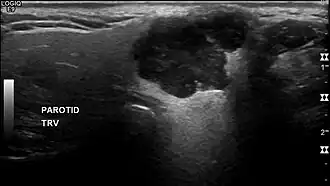

O diagnóstico imaginológico do AP envolve diversos exames de imagem, como a ultrassonografia, ressonância magnética e tomografia computadorizada (TC).[3] Pelo seu aspecto pleomórfico, o AP possui aspecto radiográfico variável e múltiplos exames podem ser utilizados para adequadamente avaliar a lesão: a TC pode oferecer a dimensão geral e o grau de invasão tecidual, especialmente óssea, enquanto a ressonância magnética auxilia a visualização de tecidos moles e invasão perineural, onde usualmente apresenta-se como uma lesão de bordas bem delimitadas de sinal hiperintenso.[1][6]

Pelo risco de recidiva tardia, entre 7 a 10 anos (mas podendo chegar a 24 anos), recomenda-se monitorar anualmente o paciente operado através de ultrassonografia.[3][15][16]